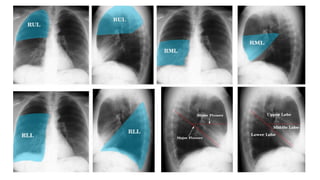

Right upper lobe consolidation

Bulging right horizontal fissure with right upper lobe

consolidation and air bronchograms.

consolidation within the postero-inferior aspect of

the right upper lobe immediately abutting the

horizontal fissure

Right middle lobe consolidation

Right lower lobe consolidation